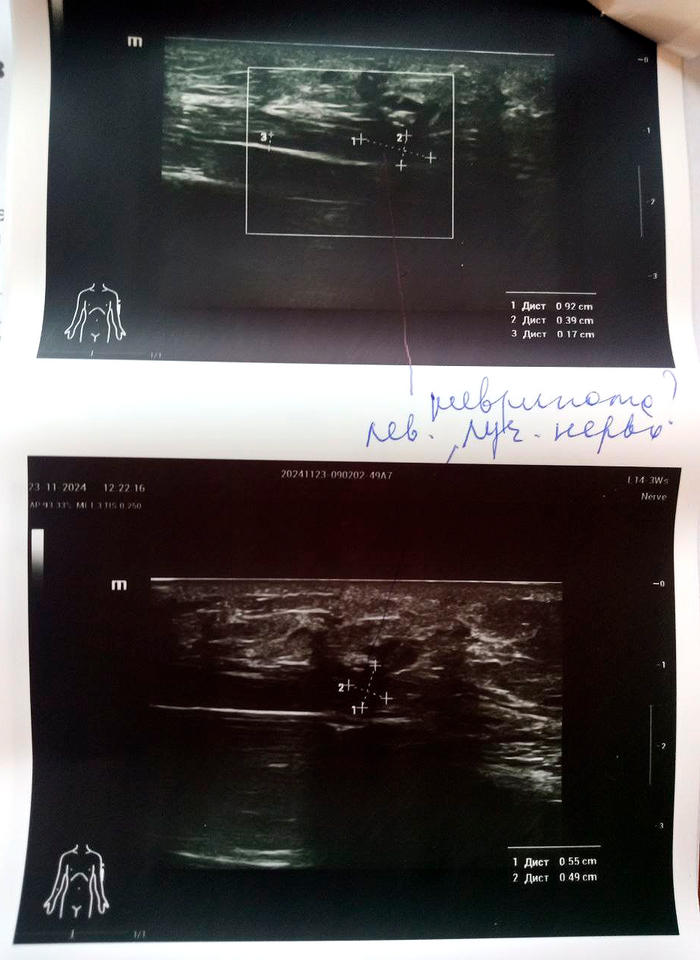

Диагноз невропатолога Комплексный регионарный болевой синдром подтверждён. Руку не отрезаем, нервы не трогаем, посттравматическая нейропатия лучевого нерва под вопросом.